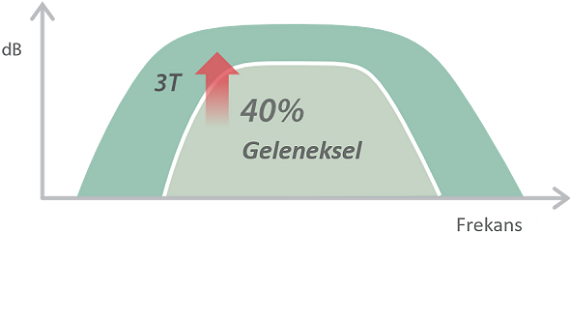

X-Insight, daha geli?mi? g?rĂŒntĂŒler elde etmek i?in kapsaml? bir ??zĂŒmdĂŒr.

Mindrayâin yeni ??zĂŒmĂŒ, geli?en en yeni ultrason teknolojileri ile birlikte, mĂŒ?terilerin g?rĂŒ?lerini klinik gerekliliklerle tam anlam?yla birle?tiren bir ??zĂŒmdĂŒr. Taptaze bir ruhla, gelece?e odaklanarak ve s?n?rs?zl???n pe?inde ko?arak, artan ?l?eklenebilirlikte sĂŒrekli olarak geli?en bir ??zĂŒmdĂŒr.

MĂŒ?teri gereksinimlerine y?nelik g?rĂŒ?ler temelinde, X-Insight'l? DC-60 Exp, eXpress Clarity, eXceptional Intelligence ve eXceeding Experience ile gĂŒ?lendirilerek, hassas g?rĂŒntĂŒlemeyle yĂŒksek verimlilik sa?layacak ?ekilde tasarlanm??t?r.